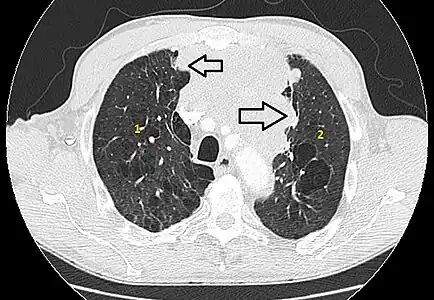

- Aspect scannographique

Présentation tomodensitométrique classique d'un thymome à un stade précoce (cercle rouge). À l'arrière, l'aorte, la veine cave supérieure et l'artère pulmonaire sont visibles en coupe.

Scanner injecté, en fenêtre médiastinale, montrant un carcinome thymique envahissant les structures médiastinales :

1 : tumeur hétérogène, aux contours irréguliers, présentant des plages hémorragiques ;

2 : veine cave supérieure ;

3 : tronc artériel brachiocéphalique ;

4 : artères sous-clavière gauche et carotide commune gauche ;

5 : crosse de l'aorte ;

6 : sternum.- Scanner en fenêtre parenchymateuse, montrant un carcinome thymique envahissant les poumons (avec des lésions d'emphysème) au contact des deux poumons (1 : poumon droit ; 2 : poumon gauche) ;

flèches noires : zones suspectes d'envahissement.